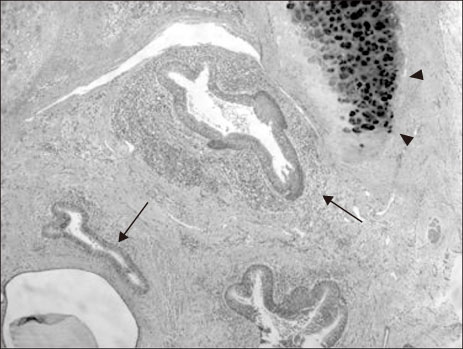

Fig. 2

Upper gastrointestinal contrast study revealed a dilated esophagus proximal to a distal esophageal stenosis (arrows). (A) Anteroposterior view. (B) Lateral view.

Fig. 2 Upper gastrointestinal contrast study revealed a dilated esophagus proximal to a distal esophageal stenosis (arrows). (A) Anteroposterior view. (B) Lateral view.